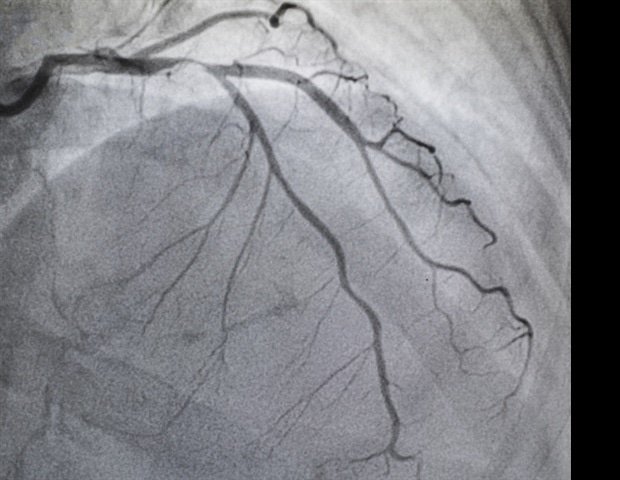

Patients with blocked or narrowed arteries often undergo PCI, where a stent is placed to restore blood flow. These patients are often treated with oral antiplatelet drugs to reduce the risk of thrombosis. If subsequent surgery is required, oral antiplatelet therapy may need to be discontinued to balance the risk of bleeding and blood clots. In these situations, clinicians may choose to use a bridging IV antiplatelet drug, such as cangrelor, in the period leading up to surgery. Cangrelor is a short-acting antiplatelet drug. In clinical practice, it is used to suppress platelets during periods when oral antiplatelet drugs are discontinued. This can occur when a patient undergoes surgery. However, real-world data describing the use of cangrelor for perioperative antiplatelet cross-linking after PCI and associated clinical outcomes remain limited.

Researchers utilized a network of cardiologists and cardiothoracic surgeons in the United States to perform a retrospective chart review (January 2020 to November 2025) of adults who received cangrelor for subsequent surgery within 6 months after PCI. Clinical outcomes (major cardiovascular events (MACE), mild, moderate, or severe bleeding events, and other complications) were characterized up to 72 hours after surgery or death. Outcomes were summarized overall and by surgical characteristics and infusion rate for the bridging dose (0.75 mcg/kg/min) evaluated in the randomized controlled trial.